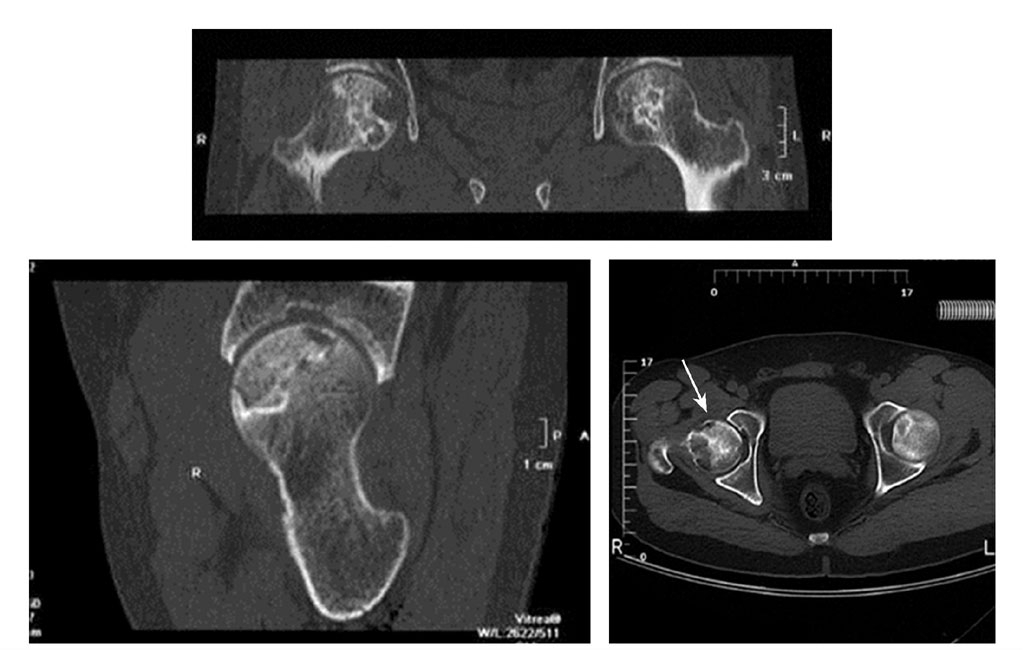

(五)CT扫描

CT扫描可清楚显示坏死病灶及修复情况及软骨下骨折(↑)

对Ⅰ期骨坏死的诊断无价值,但可清楚显示Ⅱ、Ⅲ期坏死灶的边界、面积、硬化带、病灶的修复状态及软骨下骨折情况。清晰度与阳性率优于MRI及X线片。确定有否软骨下骨折,轴位价值最大,其次为冠状位,矢状位最差。